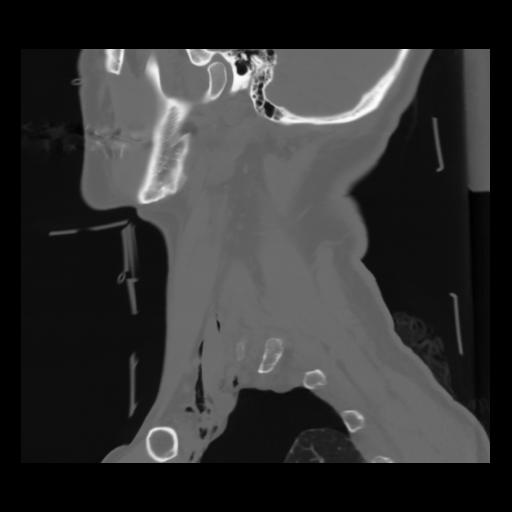

14 P.BLANDAS,,Sagittal,2.000,P.BLANDAS,Sagittal,